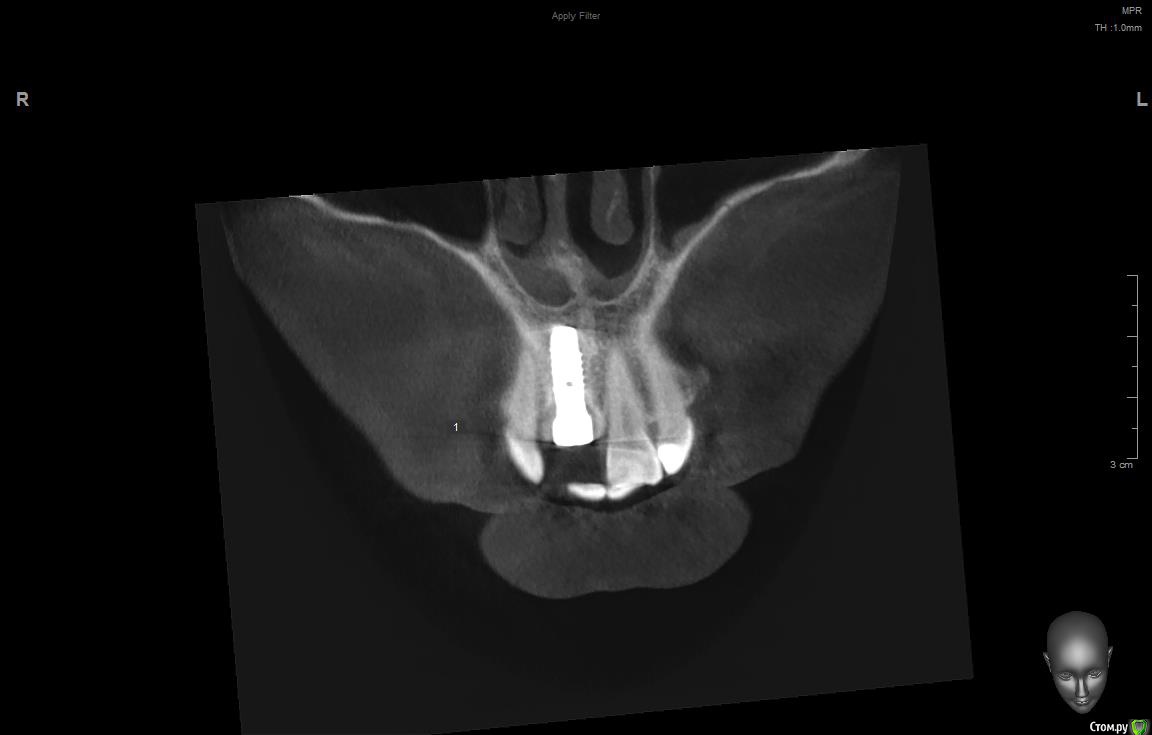

jm3300 Опубликовано 11 сентября, 2019 Поделиться Опубликовано 11 сентября, 2019 Имплант( система, производитель) не известен, формирователи подобные не видел, шестигранные отвертки не подходят( на формике отверстие под четырехгранник). Данных на имплант у пациента нет. В клинике, где ставили, якобы, не помнят что ставили. Может кто встречался с ними? Ссылка на комментарий

АнтонТЛТ Опубликовано 11 сентября, 2019 Поделиться Опубликовано 11 сентября, 2019 (изменено) Что за мода выкладывать срезы Кт, на которых всё фонит. Лучше уж прицельный снимок. Возможно это конмет, у них квадратный шлиц. Изменено 11 сентября, 2019 пользователем АнтонТЛТ 2 Ссылка на комментарий

dr Alexandr Опубликовано 14 сентября, 2019 Поделиться Опубликовано 14 сентября, 2019 Похож на Конмет, у этой системы своя протетика и ортопедический набор! Отвёртка у них 6 гр только меньше, нужно попробовать выкрутить фдм, там понятнее будет 1 Ссылка на комментарий